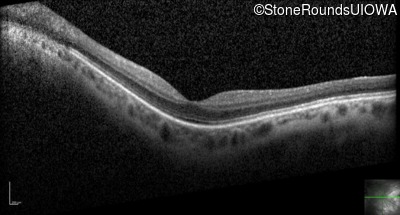

Optical Coherence Tomography - Left - 20/25 +2

Exemplar / OCT Stack

OCT Stack